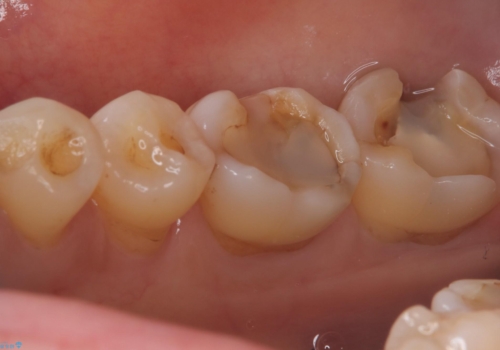

- 主訴:プラスチックの劣化が気になる。

咬合面にCR(コンポジットレジン)修復が広範囲にされており、劣化のしにくさや審美性からセラミックインレーでのやり替えとなりました。

今回残存歯質量から破折のリスクを説明し、クラウンでのやり替えも提案しましたが歯質切削量が多くなることから一度インレーで様子を見ることとなりました。